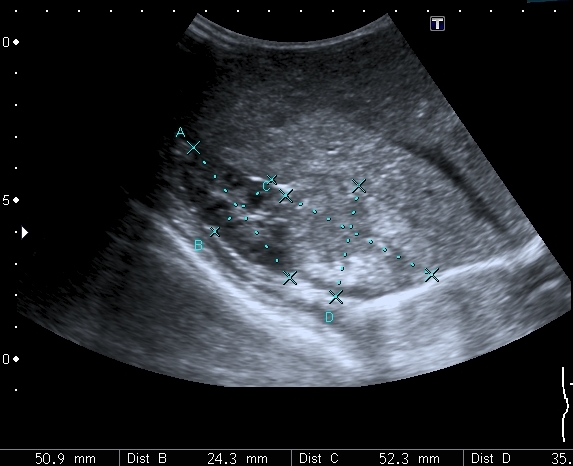

Правый надпочечник представлен округлым гиперэхогенным тканевым образованием с участками кальцификации, гиповаскулярным по отношению к ткани печени и почки

Моё заключение: нейробластома правого надпочечника с тотальным метастатическим поражением печени. Прошу членов форума высказать своё мнение о случае. Постараюсь отследить верификацию.

Верифицированный морфологически диагноз: С74.9 Низкодифференцированная нейробластома правого надпочечника с метастатическим поражением печени и костного мозга. T2N0M1, IVS стадия.